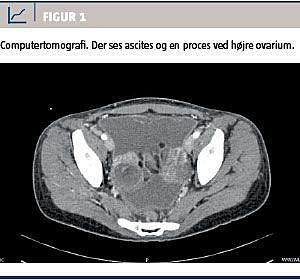

Ved en objektiv undersøgelse fandt man abdomen meteoristisk, øm under højre kurvatur og i højre flanke, men ikke peritoneal. Temperaturen var 36,9 °C målt rektalt. Biokemisk fandt man et C-reaktivt protein-niveau på 68 mg/l (referenceværdi: < 10 mg/l) og et hæmoglobinniveau på 6,5 mmol/l (referenceværdi: 7,1-9,3 mmol/l). En røntgenoversigt over abdomen viste tyndtarmsmeteorisme. Ved ultralydskanning (ULS) af abdomen fandt man en del ascites. En gynækologisk undersøgelse viste normale forhold, mens transvaginal ULS gav mistanke om en proces i højre ovarium, da dette var 5 × 4 × 5 cm stort, inhomogent og med cystiske forandringer. Patienten fik foretaget ultralydvejledt ascitespunktur, og der blev i alt udtømt fem liter gullig klar ascites, som blev sendt til cytologisk undersøgelse. Der blev målt en CA-125-koncentration på 150 kU/l (referenceværdi: < 35 kU/l). Patienten fik foretaget computertomografi af abdomen, hvorved man fandt patologisk forstørrede lymfeknuder i retroperitoneum, fortsat ascites, karcinoselignende forandringer i højre flanke og en cystisk proces i højre ovarium (Figur 1). Det gav betydelig mistanke om malign ovariesygdom.